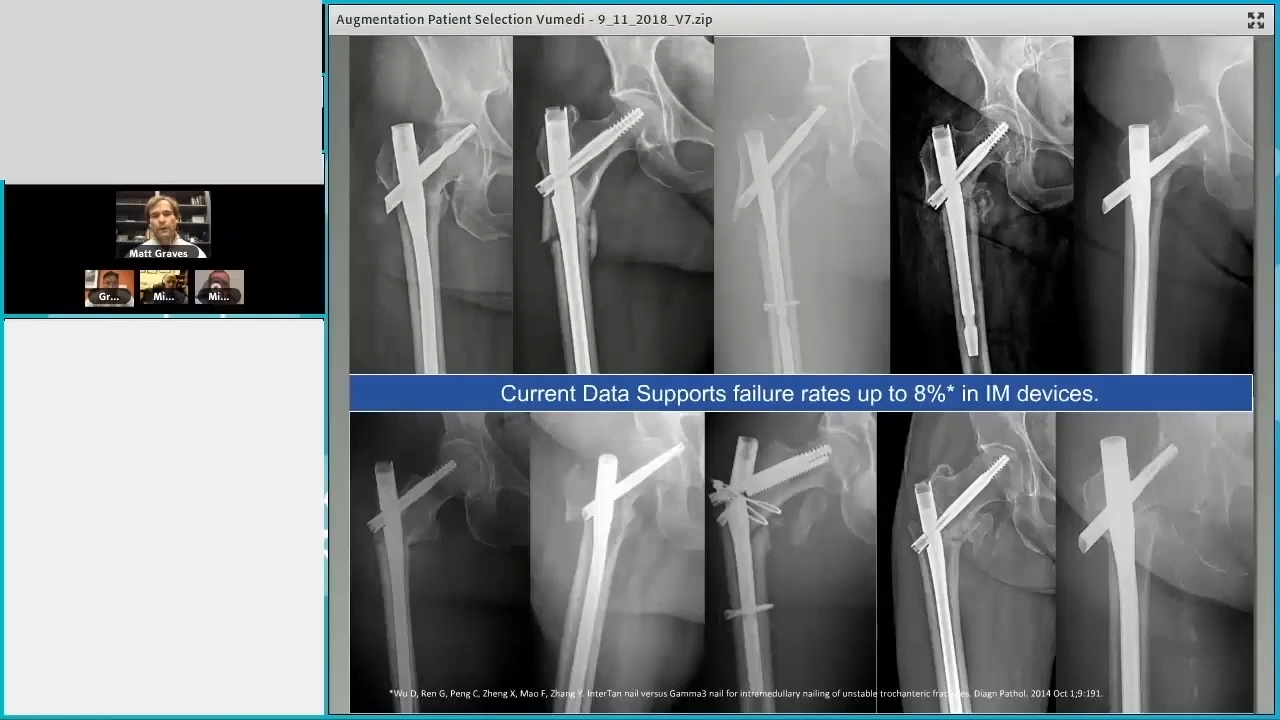

Part 1 Failure Modes